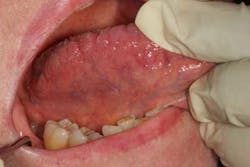

Figure 3

Hard and soft palate: Have the patient open wide and tilt his or her head backward to provide an adequate view of the hard and soft palate. If needed, depress the base of the tongue with a tongue blade to provide a better view of the soft palate. Loose teeth, red spots (figure 3), white spots, ulcerations, rough areas, asymmetry, growths, or other masses may be the first sign of a cancer in this area as in all areas of the head and neck. The uvula should hang down in the midline. Its deviation may indicate a vagal nerve palsy. Some patients have a torus palatinus, or bony outgrowth, from the midline of their hard palate. This variation of normal should not be mistaken for a malignancy.